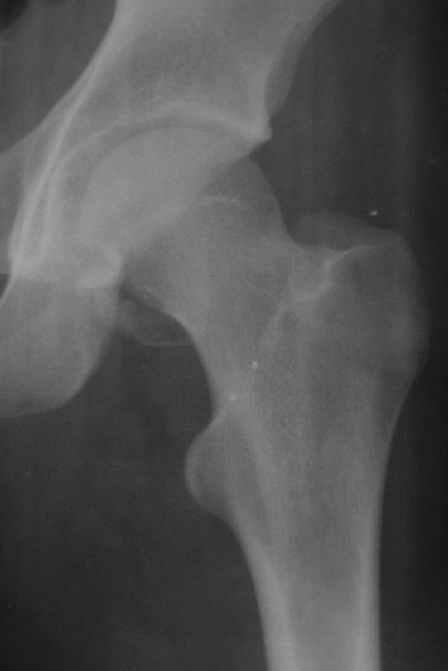

Уважаемые коллеги! Заканчивая обследование больного с переломо-вывихом бедра сделал ему обычные R-томограммы. Кажется удалось "поймать" и отломок и донорское место. Мои выводы - в скиаграмме. Считаю, что это передне-нижний фрагмент головки, образовавшийся вследствии отрывного перелома. На томограммах отломок обозначаю длинной стрелкой, а место откуда он оторвался - более короткой. Учитывая тот факт, что его размеры по КТ 25 х 15 мм считаю, что его фиксация на место необходима для профилактики артроза, что при 16-ти летнем возрасте пациента важно в плане максимального отодвигания эндопротезирования. Планирую оперировать его 24.05.05 г. Результаты представлю.

Прямой 19.05

Несколько соображений к "картинкам". На прямом снимке и КТ-томограммах все типичные линии вертлужной впадины: крыша, передняя стенка, задняя стенка - сохранены. На КТ-сканах 6 и 7 появляется фрагментация головки. С учетом R-томограмм отломок расположен спереди-снизу, а не сзади-сверху от сустава, как написано в описании КТ.